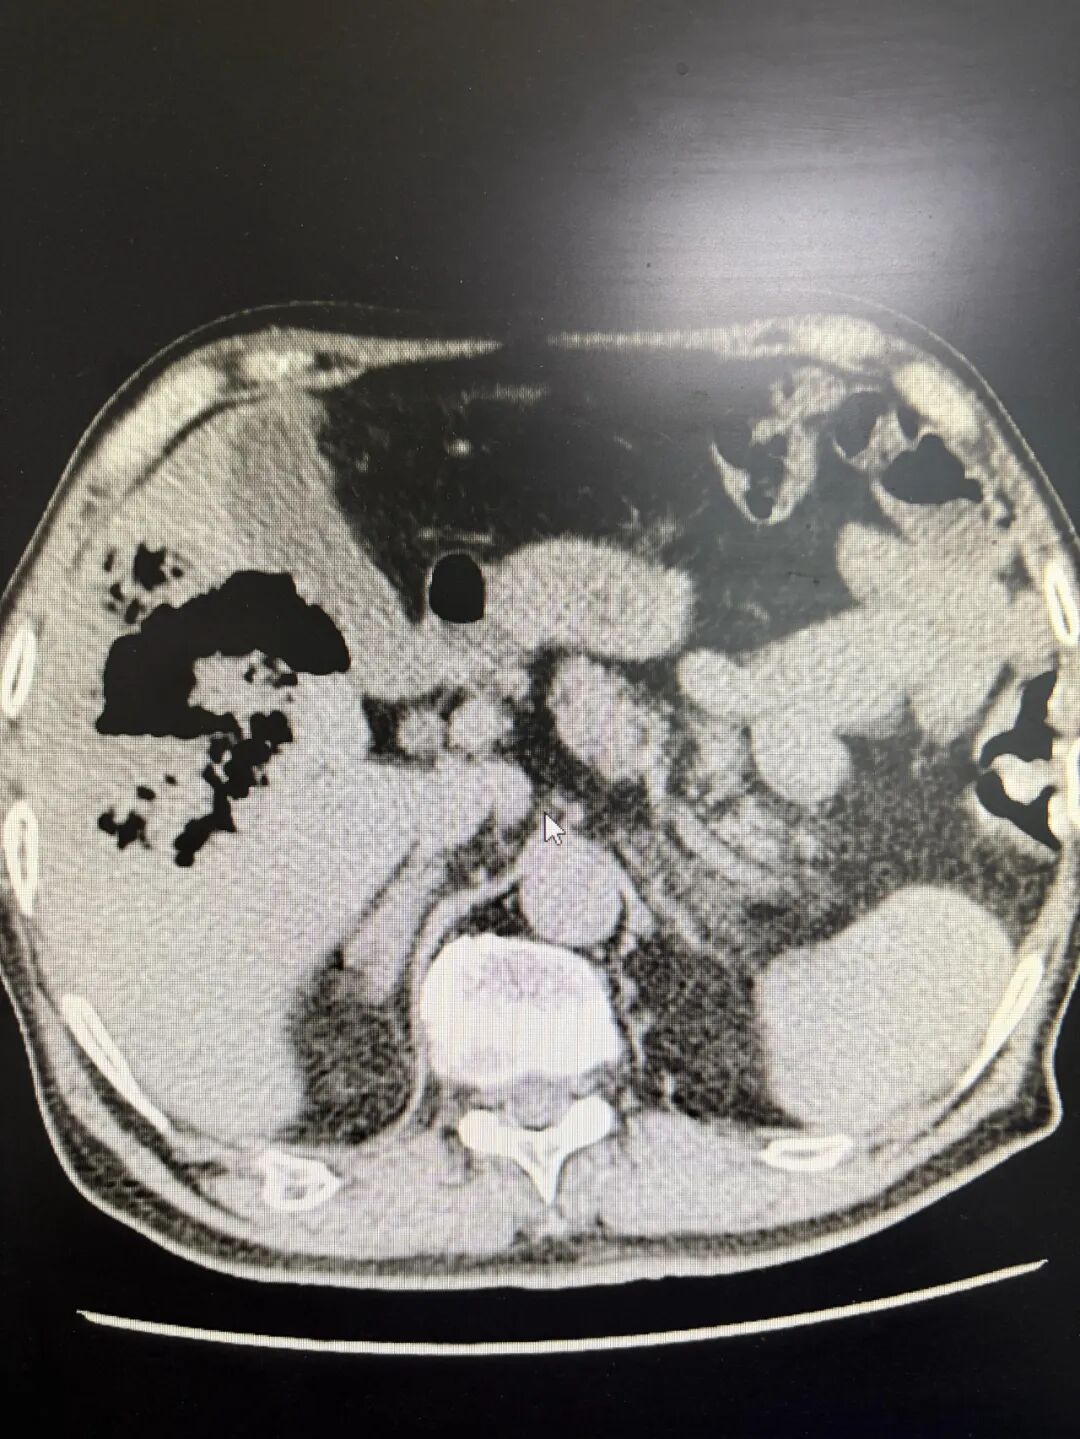

术后患者生命体征稳定,意识清醒。因脓毒血症原因,转入重症医学科继续接受高级生命支持。术后第2天患者感染指标就出现显著下降,随即转入普通病房继续治疗。影像学检查显示,术后第5天肝内胆管积气消失,脓腔明显缩小;术后第20天仅见引流管及少量积气。目前患者已顺利康复出院。

患者术后5天和20天的CT显示图